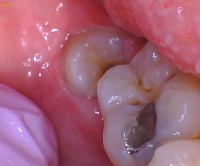

This is a real clinical picture of an upper left wisdom tooth. The chewing surface is severely discolored and black looking because it has a large cavity.